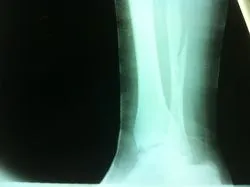

CT scan sagittal views of minimal displaced posterior tibial malleolar fracture.